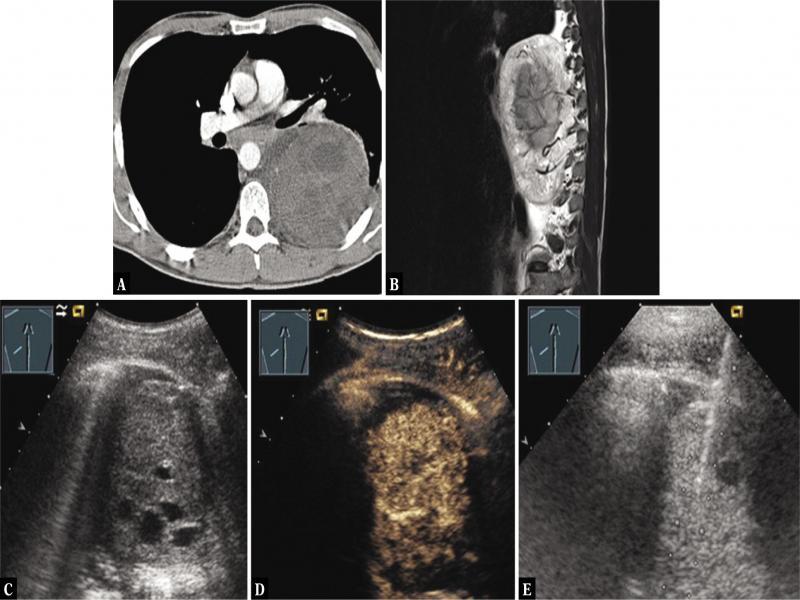

Fig. 8.

A 47-year-old male patient with a smoking history and thoracic pressure sensation, increased thoracic cutaneous vessels (A) and mediastinal tumor on chest x-ray (B). Thoracic ultrasound revealed echogenic jugular veins with slow flow, as in superior vena cava syndrome (C), and mediastinal inhomogeneous echoic tumor (D), which showed inhomogeneous enhancement with necrosis (N) on contrast-enhanced ultrasound (E). A diagnosis of bronchial carcinoma was confirmed by ultrasound-guided biopsy